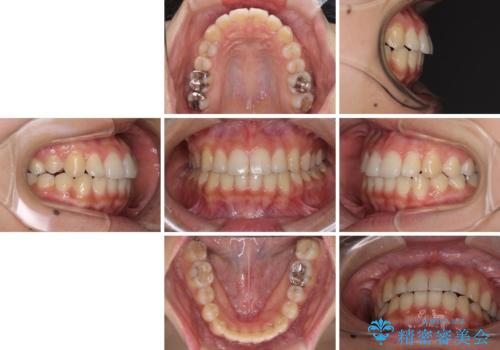

前歯の突出感とデコボコ インビザラインで改善

- 治療期間

- 1年8ヶ月

- 上下前歯のデコボコを気にして来院された患者様です。

インビザラインによる上下歯列の側方拡大と後方移動、IPR(歯と歯の間を削る)にるスペースの獲得により歯列を整えることとしました。

右上の小臼歯は歯根癒着をしており、様々な方法を試みるも動かすことができませんでした。

それでも奥歯のかみ合わせに不自由はなく、歯列をきれいに整えることができました。